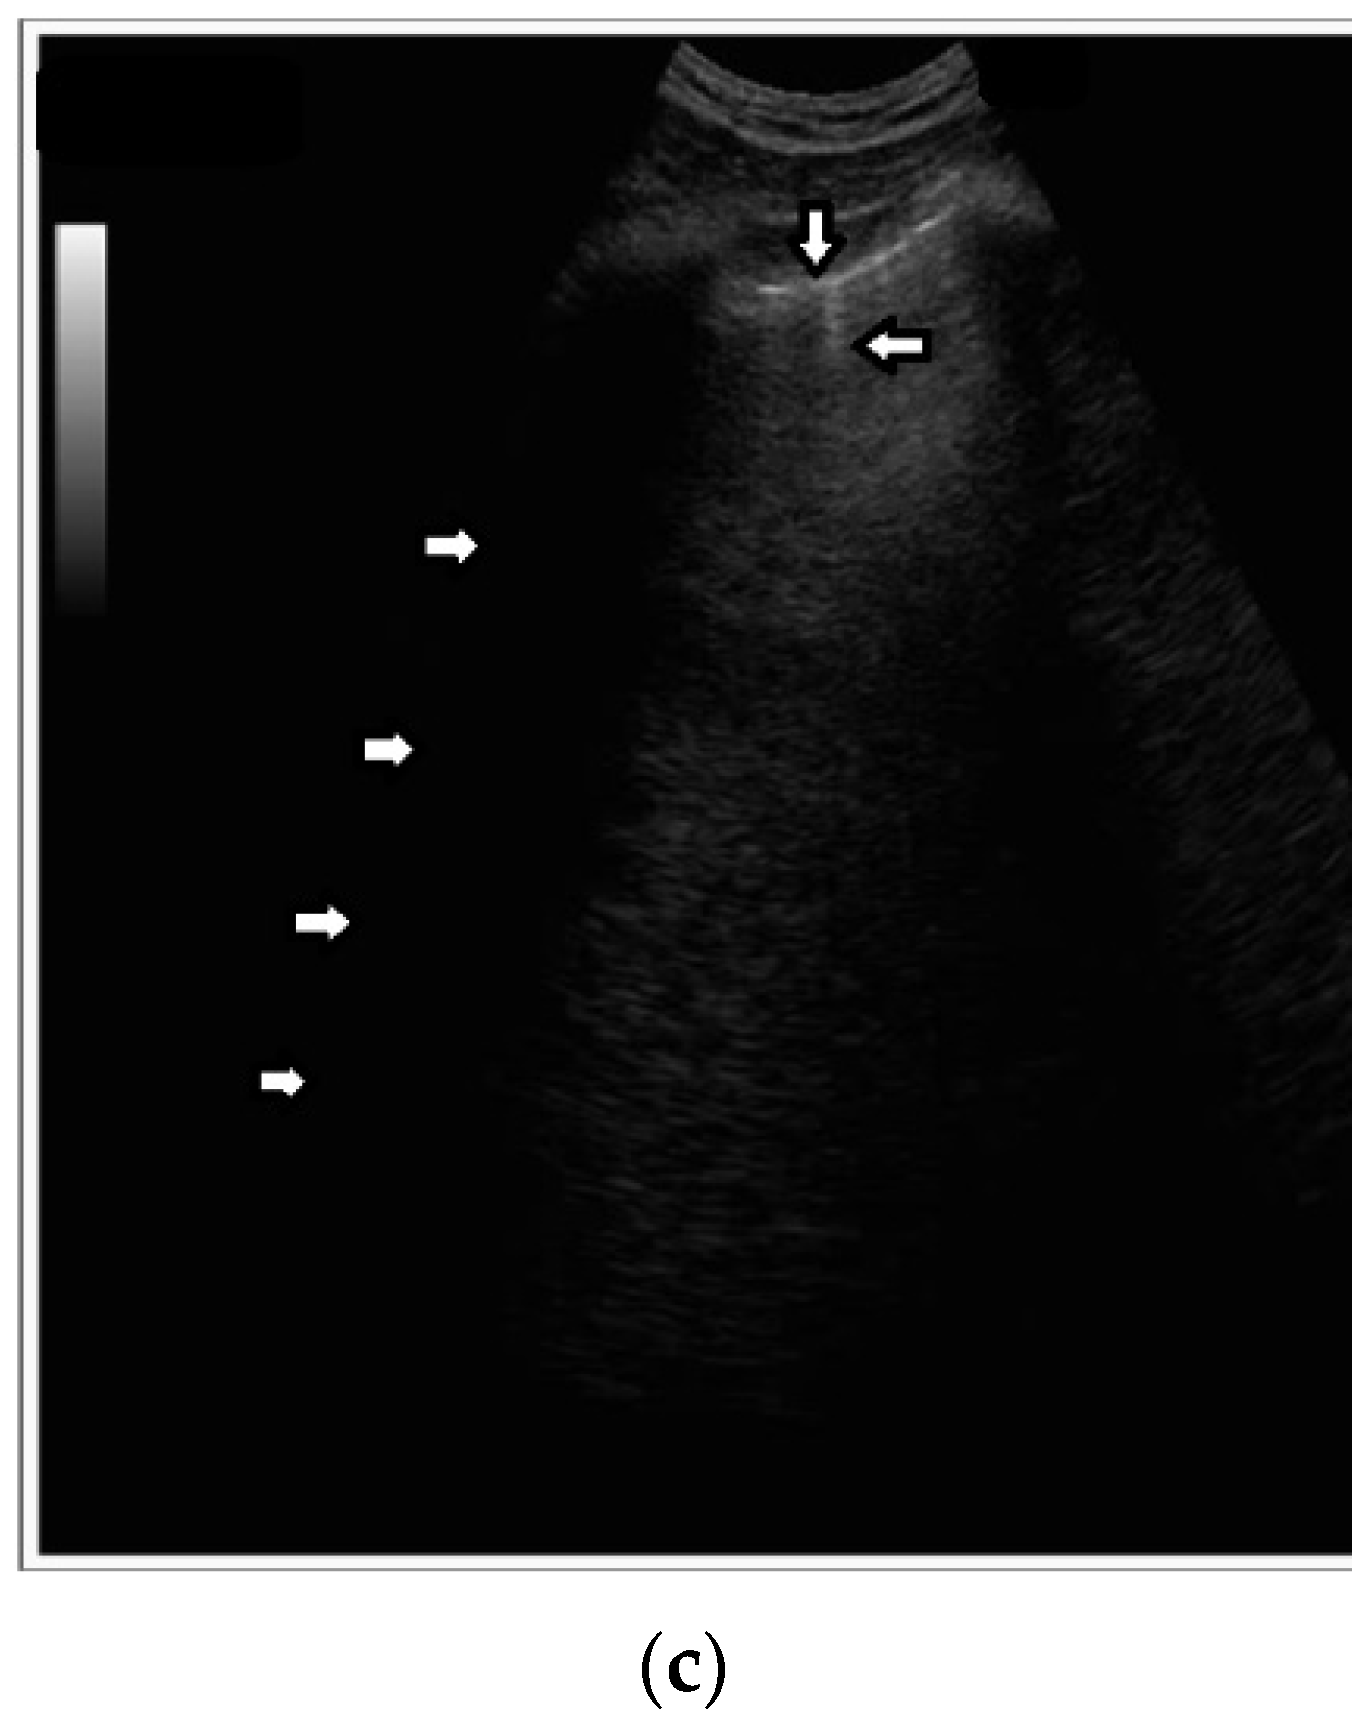

Short vertical artifacts (e.g., the so-called I or Z lines) have never been studied thoroughly. The length of vertical artifacts can vary even in the group of artifacts, which does not reach the bottom of the screen (see Figure 3a,b). One example is the early stage of developing atelectasis (during general anesthesia). What are the most important factors that influence the length of vertical artifacts?

Figure 3.

(a) Vertical artifact (←) originating from the pleural line (↓), smooth in structure, and ending after a few centimeters (a few centimeters in length). (b) Vertical artifacts (←,→) originating from the pleural line (↓), modulated sonomorphology of the artifact, and ending after a few centimeters (a few centimeters in length).

- Answer 7:

The length of an artifact, as well as its structure and its brightness, depends on so many factors that it is nearly impossible to list them all [18,19]. Generally speaking, the length of a vertical artifact is given by the time an acoustic trap needs to reradiate the pulse energy, which has been partially trapped therein previously. The length of a vertical artifact not only depends on the geometric characteristic of the acoustic trap but also on the imaging parameters. Therefore, the same acoustic trap may give rise to vertical artifacts with different lengths. The imaging parameters play a fundamental role in the formation of the artifacts and the visibility of a vertical artifact (that is, its brightness, lateral dimension, and length) depends on multiple non-orthogonal factors including the gain, the time gain compensation (TGC), and all the parameters that can be easily set by the operator from the scanner keyboard. Therefore, given the intrinsic variability of the artifacts as a function of multiple nonindependent factors, including the human factor, making an objective diagnosis on the basis of the artifactual information is a difficult task. However, going back to your primary question about the length of the shorter artifacts, I can formulate some hypotheses. First of all, we must answer another question: why are they so short with respect to the artifacts that physicians classify them as “artifacts that extend to the bottom of the screen”? Maybe their linking channel is so small that it allows the transmission of a minimal part of the pulse energy, but in this case, a modulated artifact should appear since this is the peculiarity of a small channel [20]. If a confused artifact is generated, then its minimal length can be related to a wide channel with respect to the core of the trap, which allows a quick release of the trapped energy or a dispersion of the trapped energy through lateral doorways. Attenuation can also theoretically account for a minimal length of the artifact, but in this case, I do not have a valid hypothesis on the nature of the medium.